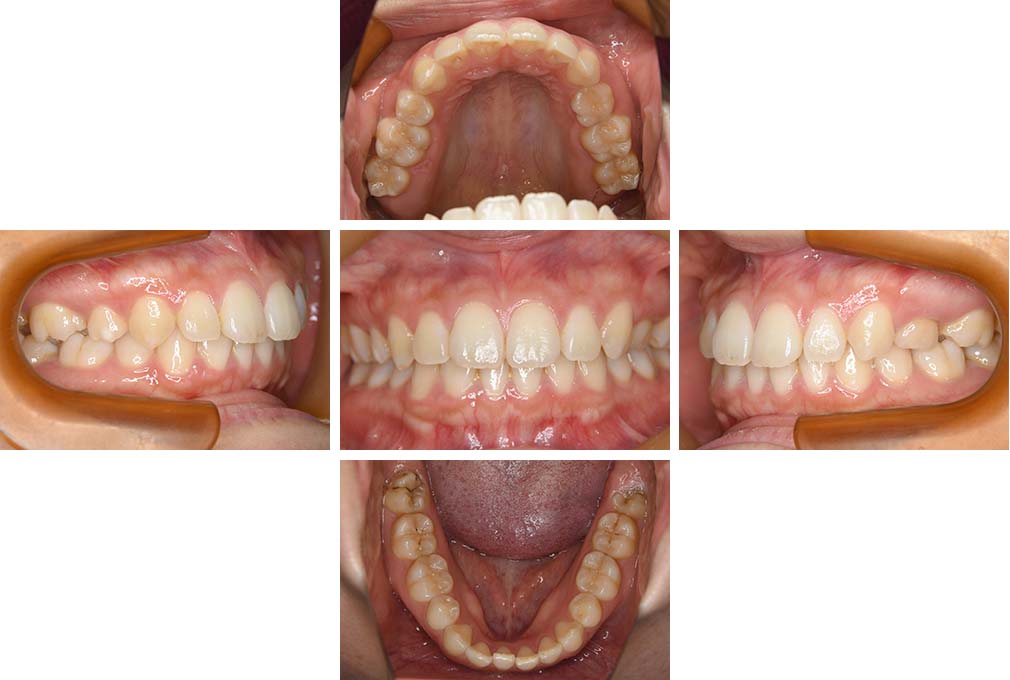

CASE:01

叢生を伴う骨格性上顎前突

初診時年齢 15歳10カ月

性別 男性

上顎前歯の前突と叢生を主訴として来院された。大臼歯関係は左右側ともにⅡ級で上顎の方が前方に位置していた。叢生を伴う骨格性上顎前突と診断し、上下顎小臼歯抜歯を行っていただきマルチブラケット装置に顎外固定装置を併用して動的治療を行った。顎外固定装置や矯正用ゴムの使用など協力状態も良好で、動的治療期間2年0カ月、調整来院20回でマルチブラケット装置を撤去し保定へ移行した。動的治療終了後10年0カ月を経過したが保定移行時とほぼ同様の咬合状態で良好な状態を保っていた。

治療前

15歳10か月

治療後

動的治療期間2年0カ月

18歳5か月

10年経過

動的治療終了後10年0カ月

28歳5か月